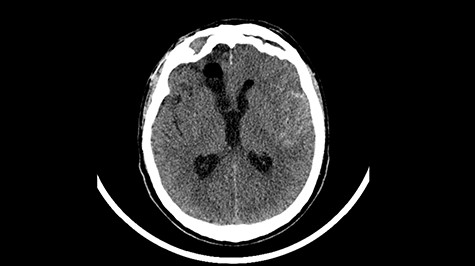

Head CT after polypectomy—seen sphenoid sinus and both maxillary sinuses filled with blood. (Department of Neurosurgery own material).

In described case, a head CT scan after polypectomy confirmed the subarachnoid hemorrhage (Fig. 1). In addition, the presence of air in the ventricular system was visible, and presence of defects of the upper left orbital wall and ethmoid on both sides (Fig. 3). In the CT scan sphenoid sinus, frontal and ethmoidal sinuses on both sides and right maxillary sinus airless, filled with blood and soft tissue. The changes also concerned the lateral part of the left maxillary sinus (Fig. 4).